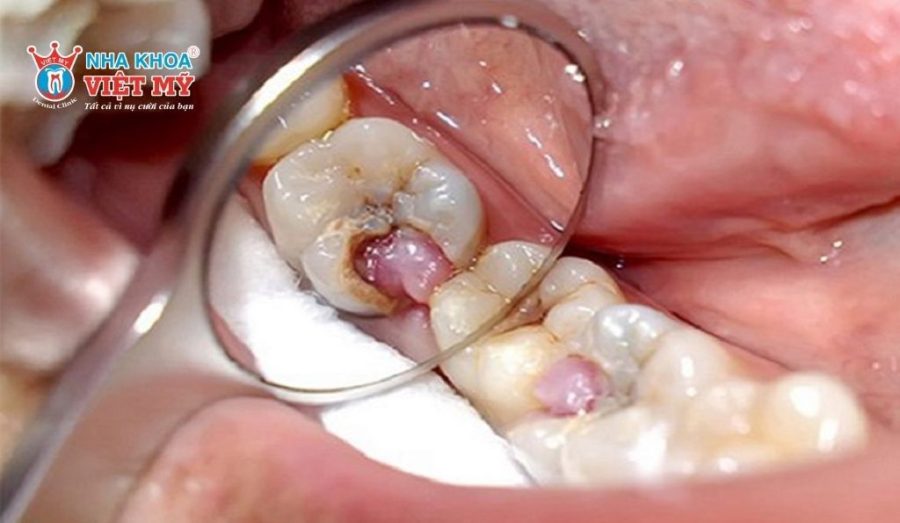

- Nhiễm trùng lan rộng: Xuất hiện các dấu hiệu nhiễm trùng nghiêm trọng như nướu sưng đỏ, có mủ, hoặc đã hình thành áp xe (viêm quanh chóp chân răng).

3.2. Nướu sưng đỏ, có mủ hoặc chảy máu bất thường

Sau khi điều trị tủy, nếu nướu quanh răng bị sưng đỏ, tấy to hoặc xuất hiện mủ trắng – vàng (áp xe), chảy máu kéo dài không dứt, đây là dấu hiệu nhiễm trùng nghiêm trọng. Mủ xuất hiện cho thấy vi khuẩn đã lan ra khỏi chóp răng, hình thành ổ viêm trong xương hàm.

Tình trạng này không nên chủ quan, vì áp xe có thể lan rộng gây sưng mặt, sốt cao, thậm chí nhiễm trùng toàn thân nếu không được xử lý sớm.